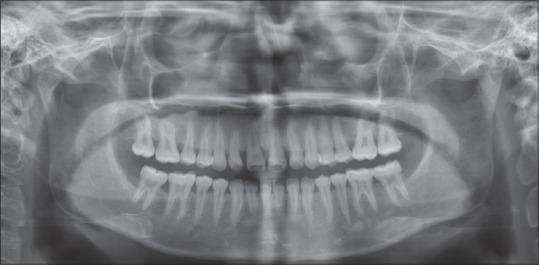

Rheumatoid arthritis (RA) is a chronic, systemic, autoimmune inflammatory disorder that is characterized by joint inflammation, erosive properties and symmetric multiple joint involvement. Temporomandibular joint (TMJ) is very rare to be affected in the early phase of the disease, thus posing diagnostic challenges for the dentist. Conventional radiographs fail to show the early lesions due to its limitations. More recently cone-beam computed tomography (CBCT) has been found to diagnose the early degenerative changes of TMJ and hence aid in the diagnosis of the lesions more accurately. Our case highlights the involvement of TMJ in RA and the role of advanced imaging (CBCT) in diagnosing the bony changes in the early phase of the disease.

类风湿性关节炎(RA)是一种慢性、全身性自身免疫性炎症性疾病,其特征为关节炎症、侵蚀性以及对称性多关节受累。颞下颌关节(TMJ)在该疾病早期很少受到影响,因此给牙医带来了诊断挑战。传统X线片由于其局限性无法显示早期病变。最近发现锥形束计算机断层扫描(CBCT)能够诊断颞下颌关节的早期退行性改变,从而更准确地辅助病变的诊断。我们的病例突出了颞下颌关节在类风湿性关节炎中的受累情况以及先进成像技术(CBCT)在诊断该疾病早期骨质改变方面的作用。